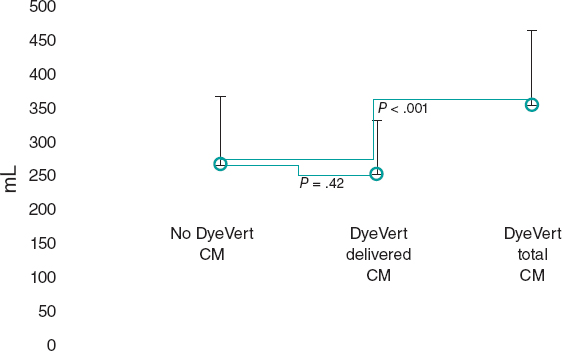

An 84-year-old female with severe aortic stenosis and previous non-disabling stroke was referred to undergo transcatheter aortic valve replacement (TAVR). The 3D computed tomography performed revealed the presence of a type 9 aortic arch with severe tortuosity (figure 1A). It was decided to protect the supra-aortic branches with suitable diameters to be able to use the Sentinel Cerebral Protection System (Boston Scientific, Marlborough, MA, United States). Manipulation length in the left common carotid artery (LCCA) was of, at least, 8 cm which is the distance between the proximal filter and the Sentinel distal edge. Figure 1B: yellow arrow: brachiocephalic trunk, 12 mm-diameter. White arrow: LCCA, 7 mm-diameter. This cerebral protection device (CPD) has a proximal filter for brachiocephalic trunk diameters between 9.0 mm and 15 mm and a distal filter for LCCA diameters between 6.5 mm and 10 mm. The angiography of the aortic arch is shown on figure 1C. This dual-system-filter basket was tried unsuccessfuly over a 0.014 in guidewire despite the use of an articulating sheath (figure 1D-F). After several attempts, a multipurpose catheter was used to engage the LCCA (figure 1G). Using a 300 cm 0.014 in guidewire, the multipurpose catheter was exchanged for the CPD which allowed its suitable deployment (figures 1H,I). The TAVR was performed successfully and the CPD was retrieved (video 1 of the supplementary data). Informed consent was obtained from the patient.

Figure 1.

The major concern is how to balance the risk of stroke after TAVR and the risk of manipulation with guidewires/catheters in supra-aortic arteries. Thus, the rigorous study of the computed tomography scan is the key factor for strategic planning purposes. This was an alternative approach to achieve the placement of a Sentinel device using a multipurpose catheter in a complex aortic arch.